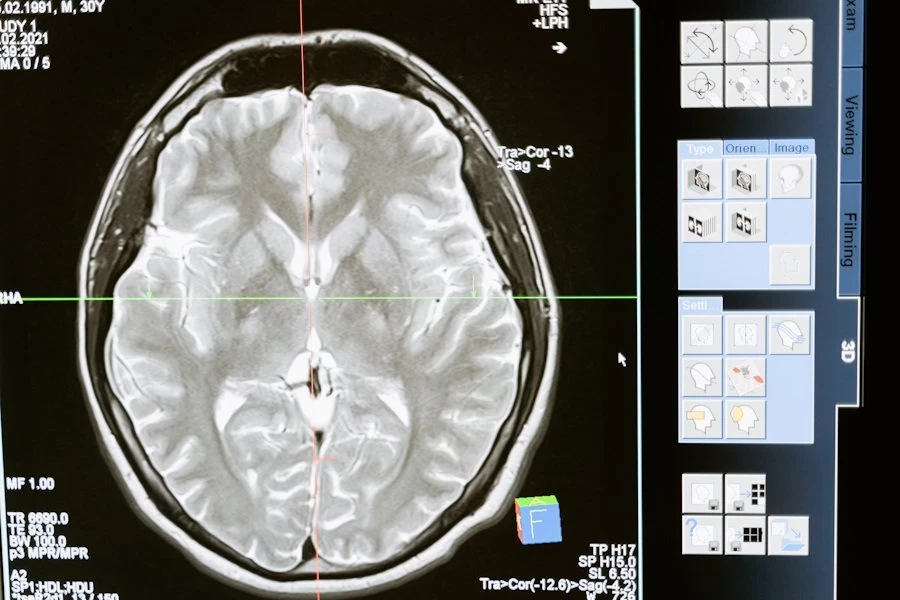

Внутримозговое кровоизлияние (ВМК), также известное как инсульт, является серьезным заболеванием, которое может иметь долгосрочные последствия и даже привести к смерти. Однако новая комбинация методов лечения, представленная Институтом глобального здравоохранения Джорджа и известная как Care Bundle, показала потенциал значительного улучшения показателей выживаемости и снижения инвалидности у пациентов, со ссылкой на The Lancet пишет SciTechDaily.